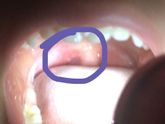

Может ещё кто то сталкивался с таким , что это у ребёнка в горле , температура поднялась до 39 , сбила до 37,5 , сейчас спит . Прошу помочь советом , я сойду с ума , написала врачу , надеюсь утром приедет если нет то мы едем в больницу

У малой температура с ночи 39 , сбила нурофенос до 37,6 . В горле какие то волдырём , первый раз такое вижу и сталкиваюсь с таким . Может вы знаете что это за болячка ? Фото прилагаю , надеюсь на вашу опытность